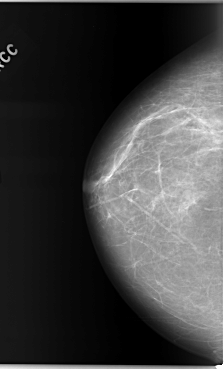

C_0103_1.RIGHT_CC

RIGHT_CC LINES 5896 PIXELS_PER_LINE 3584 BITS_PER_PIXEL 12 RESOLUTION 50 NON_OVERLAY